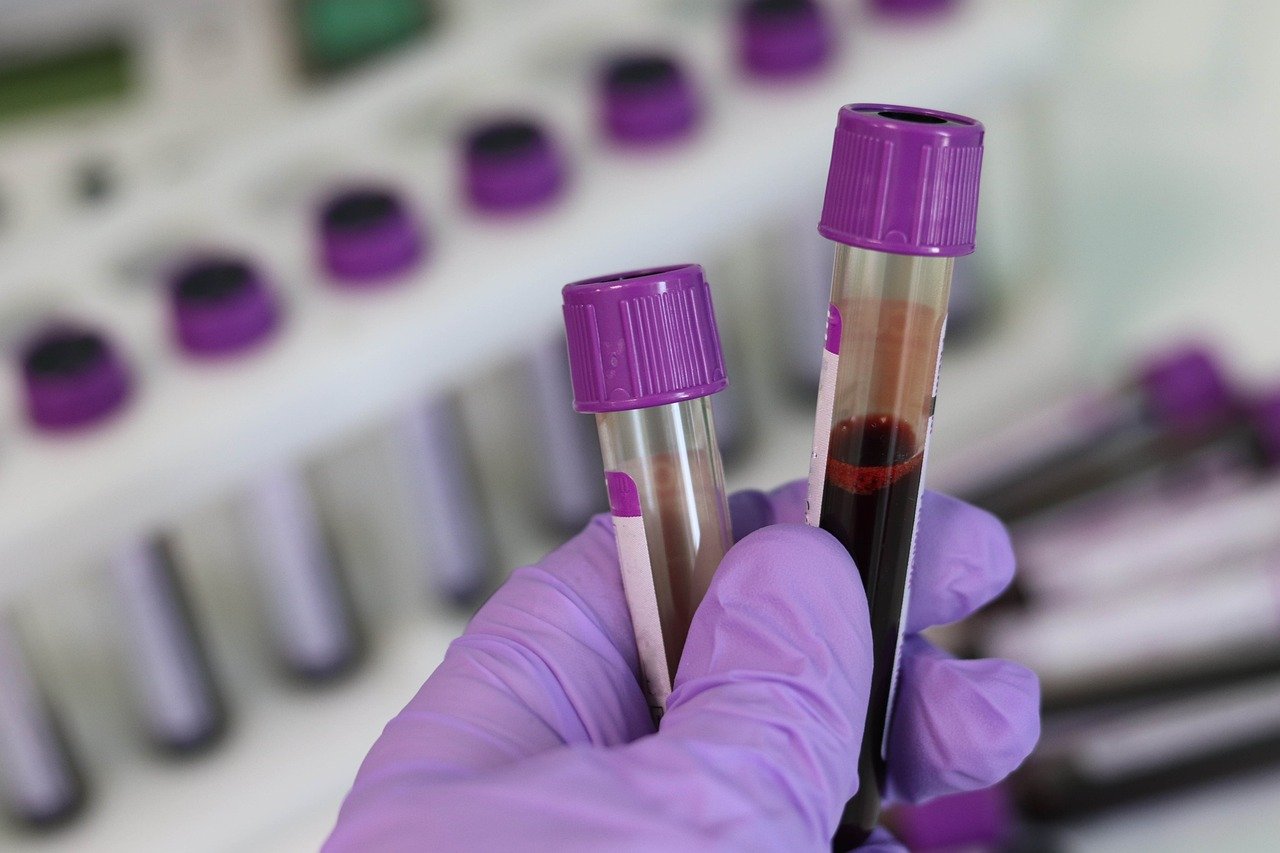

At Ruler Diagnostic Centre, we believe in empowering you with the knowledge and in sights you need to take control of your health. Our state-of-the-art diagnostic services are designed to provide you with accurate, reliable, and timely results, helping you make informed decisions about your well-being.